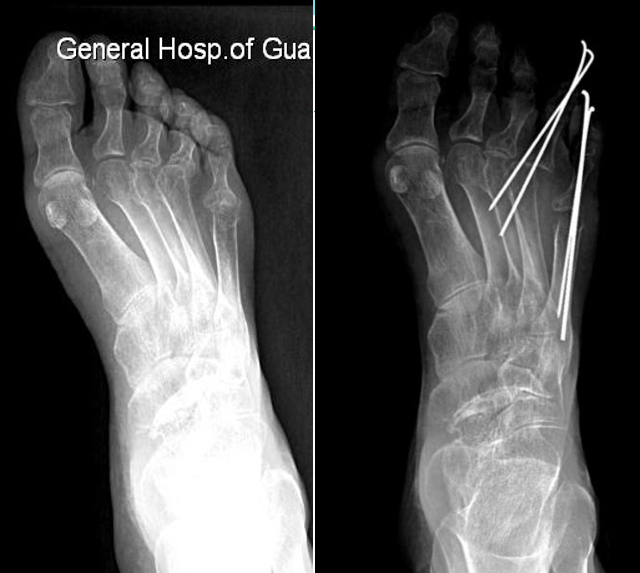

例4:罗XX,女,60Y。

左足:第1-5跖趾关节脱位,足拇外翻。

胼胝体:第一跖骨内侧,第2/3跖骨头跖侧,第5跖骨头跖/外侧。

左足:第2-5趾爪形趾。

右足:第4趾爪形趾,趾间关节胼胝,疼痛。

右足:第5跖骨头跖/外侧胼胝。

CT重建:第1跖骨头破坏。

术式:左足:第1跖趾关节融合+第2-5跖趾关节成形术;右足:第4趾间关节融合+第5跖趾关节成形术